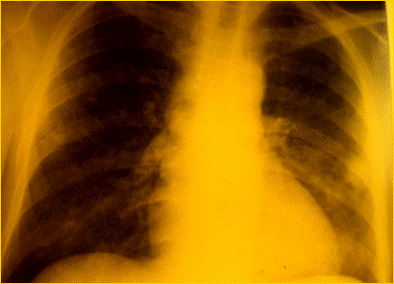

RX TORACE DI PAZIENTE AFFETTO

CARDIOMIOPATIA DILATATIVA